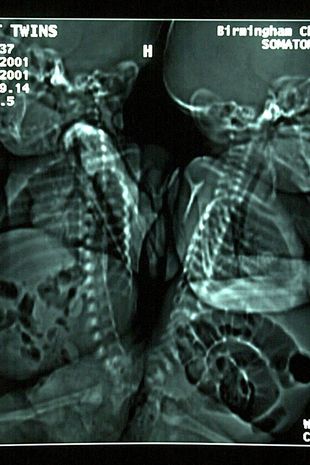

Vào năm 2001, mặc dù chỉ có 5-25% cơ hội sống sót nhưng các bác sĩ đã quyết định thực hiện ca phẫu thuật khi hai chị em song sinh Eman và Sanchia mới được ba tháng tuổi.

Vào đầu năm 2000, phẫu thuật tách cột sống là một kỹ thuật mới có tính đột phá và mới chỉ được thực hiện có 3 lần trên toàn thế giới. Mặc dù các bác sĩ lo ngại rằng ca mổ này có thể khiến hai cô bé song sinh bị bại liệt, nhưng vào năm 2001 họ đã quyết định thực hiện ca phẫu thuật khi hai chị em Eman và Sanchia mới được ba tháng tuổi.

Phép màu thực sự đã xảy ra khi ca phẫu thuật tiên phong kéo dài 16 giờ tại Bệnh viện Nhi đồng Birmingham do bác sĩ giải phẫu thần kinh quá cố Tony Hockley chỉ đạo - chưa từng được thực hiện ở Anh và chỉ hai lần trước đây trên thế giới - được tiến hành "thành công tốt đẹp", và hai chị em Eman và Sanchia có cơ hội xuất hiện trên kênh truyền hình ITV Lorraine để cảm ơn các nhân viên y tế đã giúp họ trở thành "hai người riêng biệt", và chia sẻ những khó khăn mà cha mẹ của họ phải đối mặt khi đưa ra quyết định hệ trọng đến như vậy.